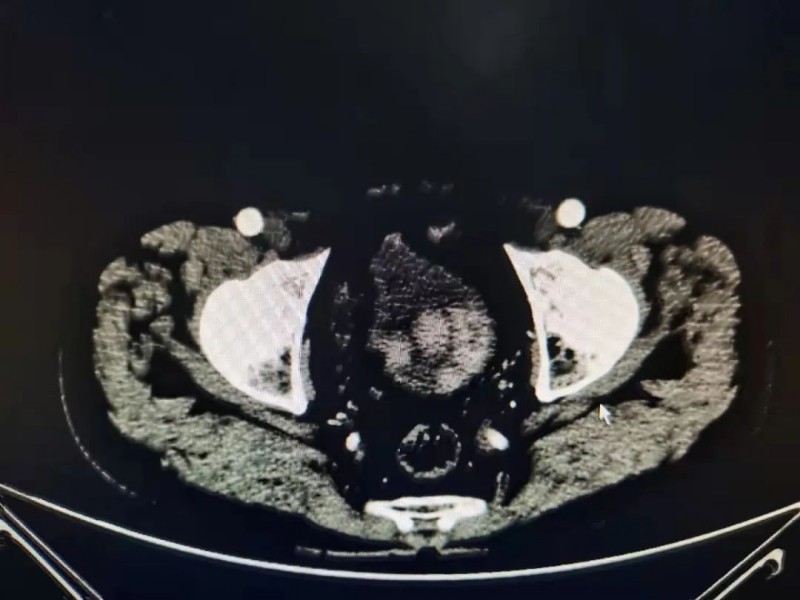

近日,凭借精湛的技术和多学科的团结协作,泌尿外科青年医师团队又成功完成1例高难度的腹腔镜下膀胱癌根治性全切+标准淋巴清扫+Braker术。患者,苟大爷,65岁,4年因解肉眼血尿于达州诊断“膀胱肿瘤”,行了膀胱肿瘤电切术,术后9月及术后2年余先后两次出现血尿症状,并分别于达州市和重庆市明确“膀胱肿瘤复发”。

病理提示:高级别浸润性尿路上皮癌,均建议其行膀胱肿瘤根治性全切术,但因苟大爷对“膀胱癌”疾病本身认识不足,以及对术后生活质量、并发症等方面的担忧,仍然选择了相对保守的“膀胱肿瘤电切术”,但事与愿违,今年2月苟大爷来我院行术后常规复查时再次明确“膀胱肿瘤复发”。

11月22日,在蔡北平主任医师的指导下,由王智民主治医师主刀,在麻醉科杨林主任医师、熊毅主治医师的精准麻醉治疗团队及手术护理团队的密切配合下成功为苟大爷实施了“腹腔镜下膀胱癌根治性全切+标准淋巴清扫+Braker术”。